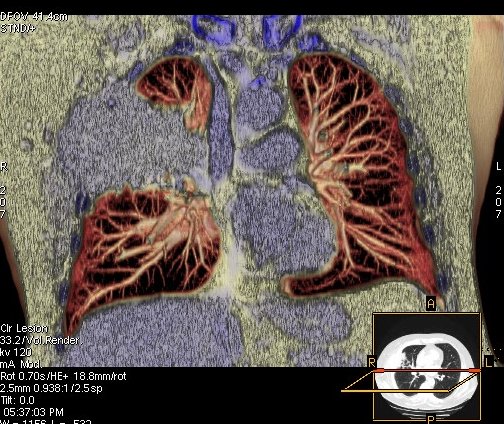

Foto: Aleksandar Ivković Foto: Aleksandar Ivković Foto: Aleksandar Ivković Strašna razlika kod pluća pušača i kovid pozitivne osobe autor: Božica Luković Zdravlje 23. jan. 2021. 12:06 > 23. jan. 2021. 12:15 0 Podeli vest: Radiolog Aleksandar Ivković od početka pandemije daje korisne informacije o svim aspektima kovida 19. On je nedavno uporedio rendgen snimke pluća zdrave osobe, pušača, osobe koja je zaražena gripom H1N1, a onda i osobe koja ima kovid 19. Razlike su zapanjujuće. Podeli vest: Oglas Objavu doktora Ivkovića sa njegovog bloga "Ljudi i ostale laži" prenosimo u celosti."Nedavno sam video u medijima da je neko preneo rdg sliku i razlike kod nalaza zdrave osobe, pušača i bolesnog od kovida 19. Kako nisam baš previše zadovoljan onim što je prikazano, evo kako to izgleda u našoj varijanti. Zdrava osoba CT nalaz kod zdrave osobe podrazumeva da ne postoje nikakvi poremećaji strukture plućnog parenhima, da su krvni sudovi uredni i da nema suženja disajnih puteva, kao i da nema uvećanih limfnih žlezda u hilusima pluća i medijastinumu. Foto: Aleksandar Ivković | Foto: Aleksandar Ivković * Foto: Aleksandar Ivković | Foto: Aleksandar Ivković Zdrava muška osoba mesec dana nakon zapaljenja pluća tokom kovida 19. Nalaz bez nekih posebnih problema iako se naziru tragovi zapaljenja. Snimak u boji je zdrava osoba, nepušač, bez ikakvih bolesti pluća u istoriji. Grip H1N1 Pokazaću samo drastične nalaze kod gripa H1N1, to je znači onaj grip koji je izazvao epidemiju španske groznice i epidemiju 2009. godine koja još uvek nije prestala (svake godine imamo makar 15%). Foto: Aleksandar Ivković | Foto: Aleksandar Ivković * Foto: Aleksandar Ivković | Foto: Aleksandar Ivković * Foto: Aleksandar Ivković | Foto: Aleksandar Ivković * Foto: Aleksandar Ivković | Foto: Aleksandar Ivković Nisu svi pacijenti imali ovakve nalaze, pokazujem one koji su imali tešku kliničku sliku. Kod gripa se sve odvija obično u sedam dana. Kao što se vidi, zapaljenje je bilo jednostrano, uglavnom. Ali kada je dolazilo do pogoršanja, onda je centralno obostrano dolazilo do edema pluća. Pušenje Kod pušača postoje razne varijante nalaza na plućima. U principu nisu tako dramatične kao što su zapaljenja. Nalaz na plućima kod pušača može biti potpuno normalan. Ovo ne pišem zato što podržavam pušenje, naprotiv, veliki sam protivnik, ali iznošenje laži nikada nije dobro. Dve dijagnoze su bitne kao posledica pušenja. Prva je hronična plućna opstruktivna bolest: Foto: Aleksandar Ivković | Foto: Aleksandar Ivković * Foto: Aleksandar Ivković | Foto: Aleksandar Ivković * Foto: Aleksandar Ivković | Foto: Aleksandar Ivković Jasna je razlika u nalazu, posebno na ovim slikama u boji, gde su ta plava polja delovi pluća koji su propali zbog cigareta (može da se uporedi sa zdravim plućima iznad).Druga bolest koja je česta kod pušača je u svakom slučaju karcinom. Foto: Aleksandar Ivković | Foto: Aleksandar Ivković * Foto: Aleksandar Ivković | Foto: Aleksandar Ivković * Foto: Aleksandar Ivković | Foto: Aleksandar Ivković * Foto: Aleksandar Ivković | Foto: Aleksandar Ivković Tkivo koje raste unutar pluća i razjeda ga. Takav je nalaz kod karcinoma pluća. Često je uzrok upotreba cigareta. Kovid 19 O kovidu sam pisao puno puta. Evo nekih slika, radi poređenja. Foto: Aleksandar Ivković | Foto: Aleksandar Ivković * Foto: Aleksandar Ivković | Foto: Aleksandar Ivković * Foto: Aleksandar Ivković | Foto: Aleksandar Ivković * Foto: Aleksandar Ivković | Foto: Aleksandar Ivković Nakon što pacijent bude izlečen od gripa ili kovida 19, pluća se mogu vratiti u normalu.To je razlika u odnosu na posledice upotrebe cigareta. Ovi snimci nisu postavljeni da bi se poredile bolesti, već da bi se ukazalo kako različite bolesti deluju na pluća. I ono što je veoma važno, ako neko dobije jednu od ovih bolesti, ne znači da u toku života neće dobiti drugu.Ne pišem zato smo smatram da sam najpametniji ili najpozvaniji da objašnjavam, nisam kao neki pojedinci ubeđen da samo ja imam znanje i istinu, pišem jer drugi ćute. Pišem jer ima i puno onih koji iznose laži, mora se tome stati na put.A ovi, koji pišu da sam umro, da sam oboleo od karcinoma, ovi koji mi žele da nađem dobro grobno mesto, šta da vam kažem, vi ste mi inspiracija. Svesni ste da sam u pravu i odlično znam da ste već uradili sve da se vakcinišete i mnogi od vas će to uraditi pre mene ali i dalje ćete ubeđivati druge da se ne vakcinišu i da je dobro za njih da se razbole i umru. Ima puno reči za vas u svim našim slovenskim jezicima, znate vi sami šta ste", piše dr Ivković.***Bonus video:https://youtu.be/MWucTT0qBsIPratite nas i na društvenim mrežama:FacebookTwitterInstagram Dr Lukić otkrio spisak svih antibiotika za kovid upalu pluća Zdravlje 0 Dr Žujović: Kako oporaviti pluća posle korone Zdravlje 0 Pet znakova da ti je kovid zahvatio pluća Zdravlje 0 Virusolog Ana Banko ruši veliku zabludu o ruskoj vakcini Emisije 0 aleksandar ivković korona kovid pluća snimak pluća Pratite nas na društvenim mrežama: Koje je tvoje mišljenje o ovoj temi? Učestvuj u diskusiji ili pročitaj komentare Budite prvi koji će ostaviti komentar Pošalji komentar Pročitaj komentare (0)